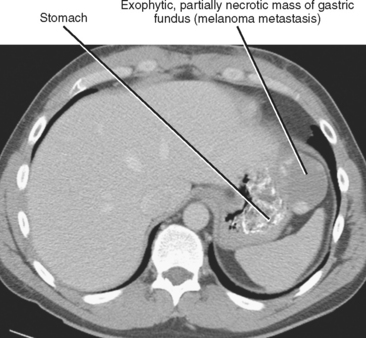

Thick tortuous folds or lobulated filling defects in the cardia or fundus. Right gastroepiploic artery inferiorly and left gastroepiploic artery and short gastric arteries superiorly fundus of the stomach. Results of surgical treatment of carcinoma of the esophagus and gastric cardia. The collection of cases presented here comprises only that material which is rare in our experience or quite new to us.

Cain jc jordan gl jr comfort mw gray hk. J am med assoc. The gas tric fundus is dened as the portion of the stomach craniad to the gastric car dia. Commonly accompanying this are abnormally dilated short gastric veins which pass from the splenic vein to encircle the gastric fundus and form gastric fundal varices.